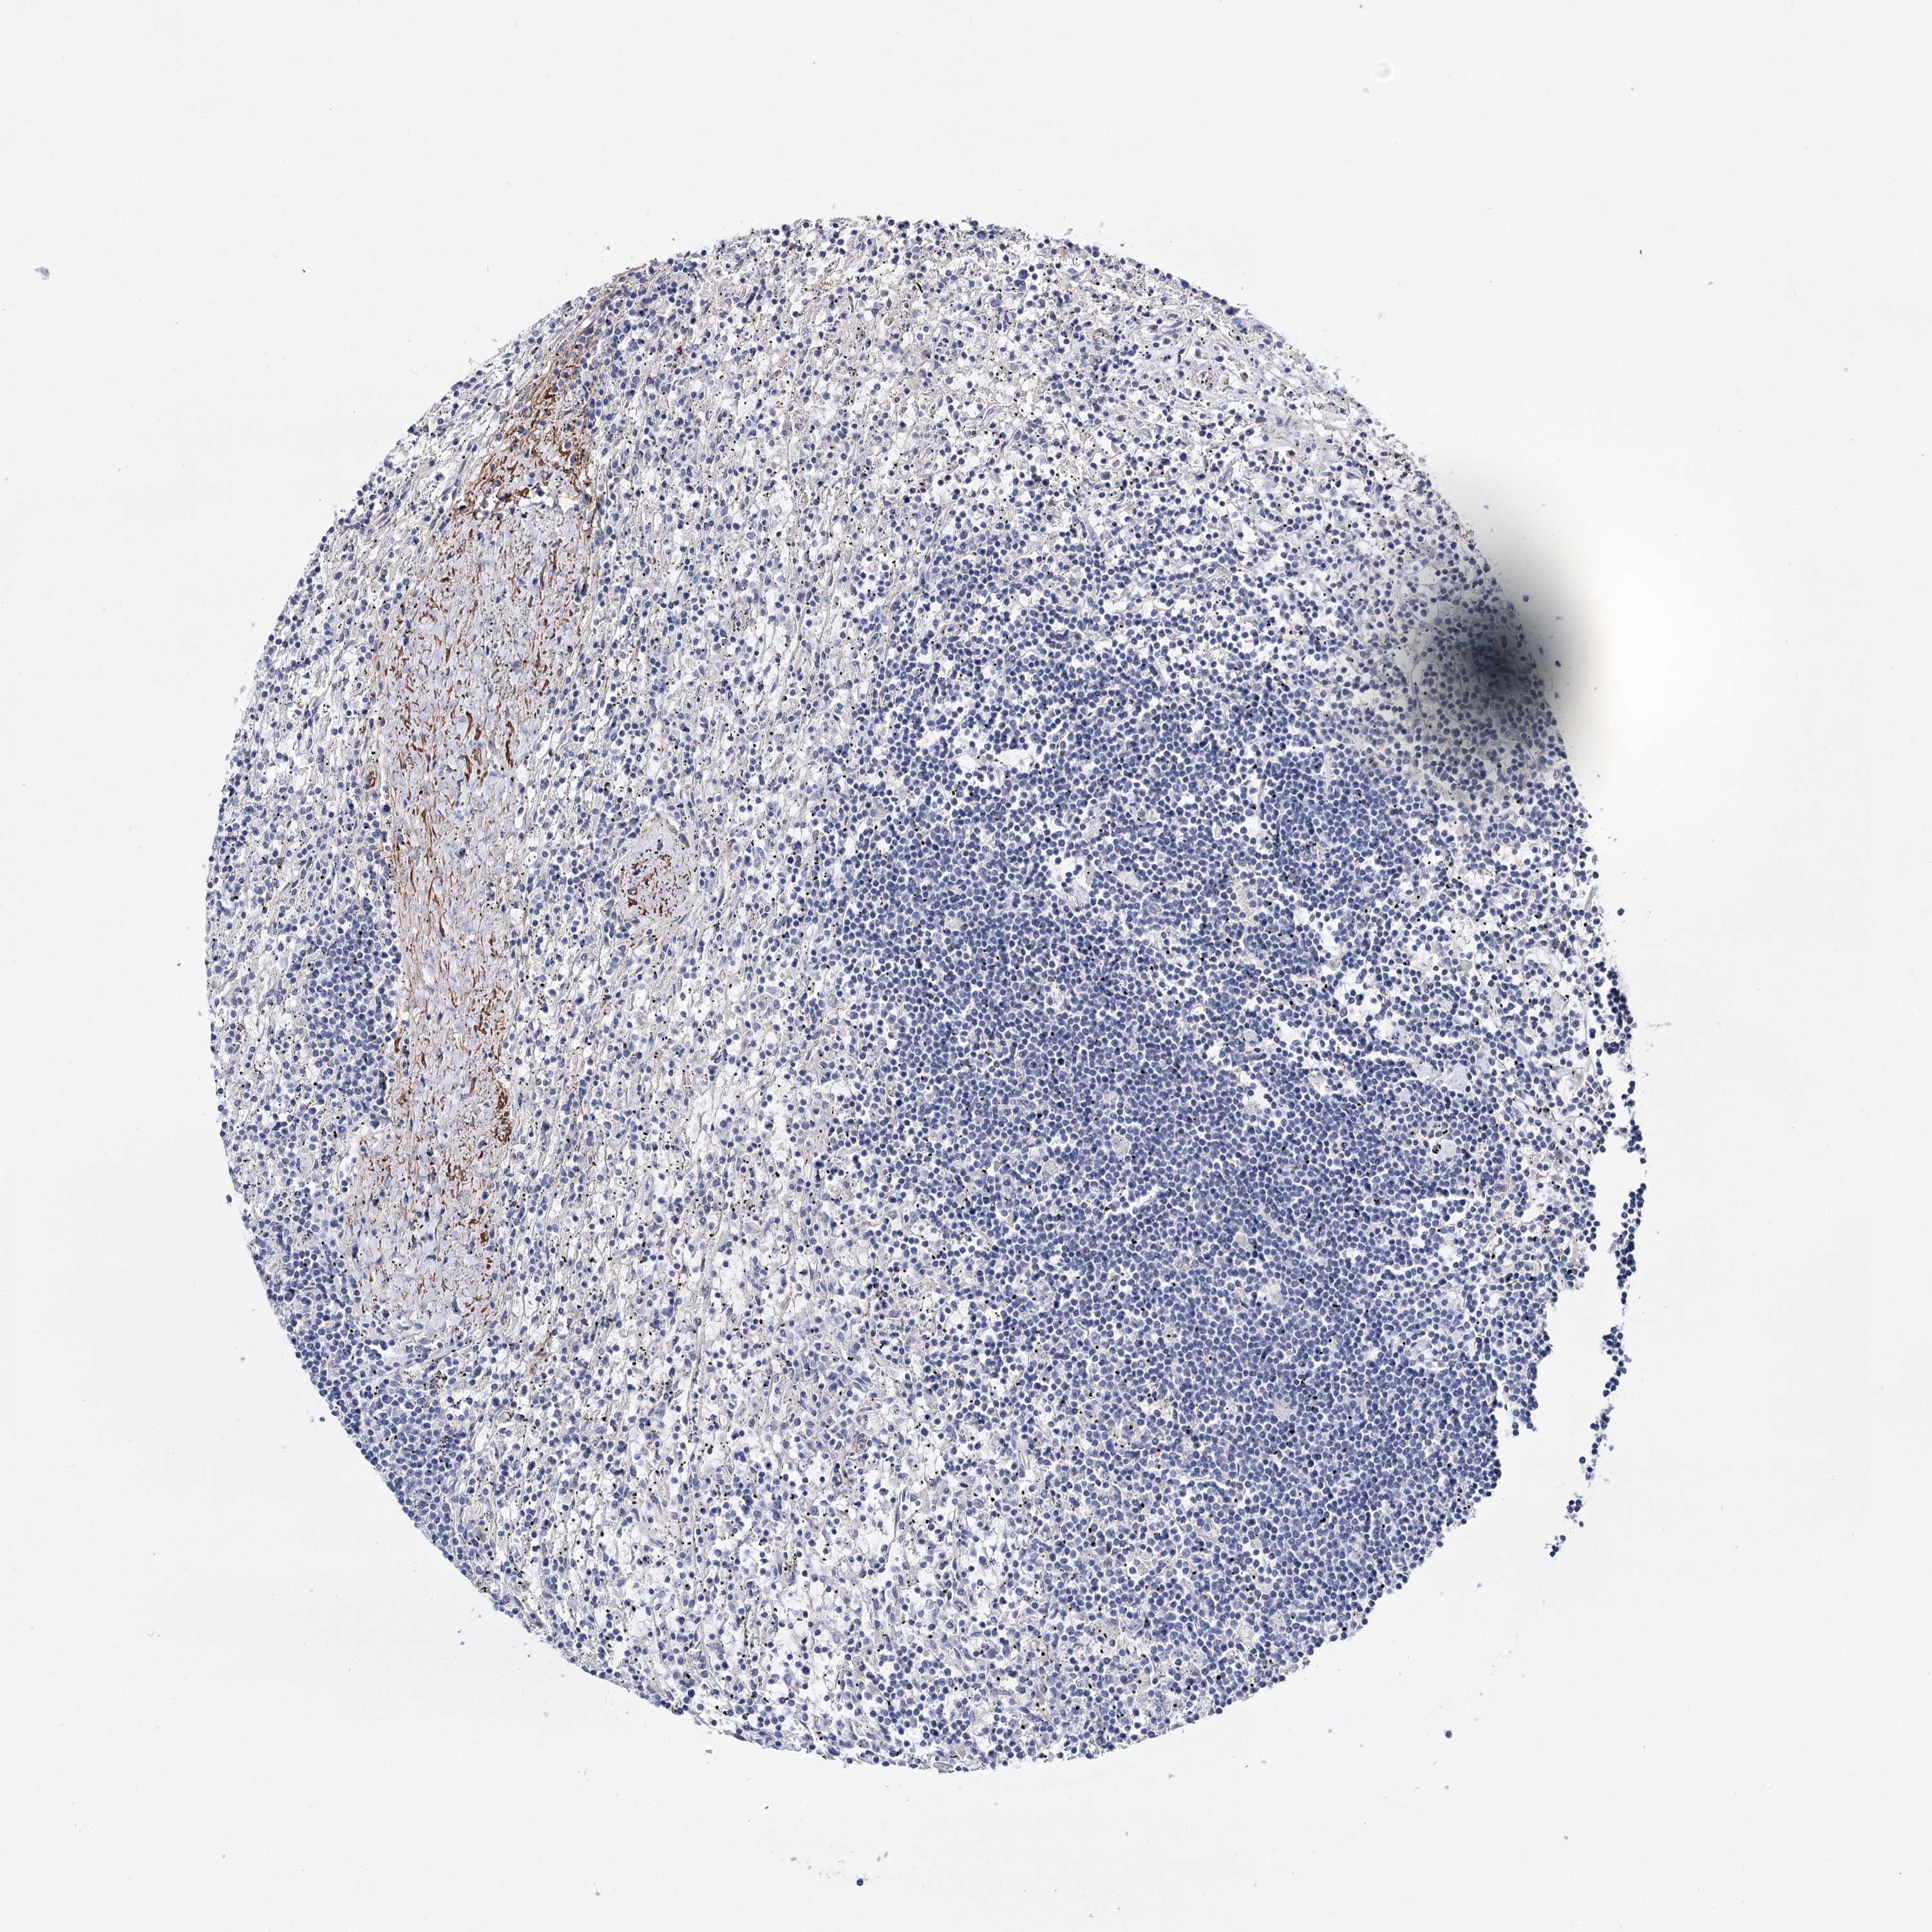

CANCER LYMPHOMA Show tissue menu

LYMPHOMA - Protein expressioni

A mouse-over function shows sample information and annotation data. Click on an image to view it in a full screen mode. Samples can be filtered based on level of antibody staining by selecting one or several of the following categories: high, medium, low and not detected. The assay and annotation is described here.

Antibody stainingi

Antibody staining in the annotated cell types in the current human tissue is reported as not detected, low, medium, or high, based on conventional immunohistochemistry profiling in selected tissues. This score is based on the combination of the staining intensity and fraction of stained cells.

Each image is clickable and will lead to virtual microscopy that enables deeper exploration of all samples and also displays staining intensity scores, fraction scores and subcellular localization as well as patient and tissue information for each sample.

Antibody HPA038867

Hodgkin's disease, NOS

Malignant lymphoma, non-Hodgkin's type, High grade

Malignant lymphoma, non-Hodgkin's type, Low grade